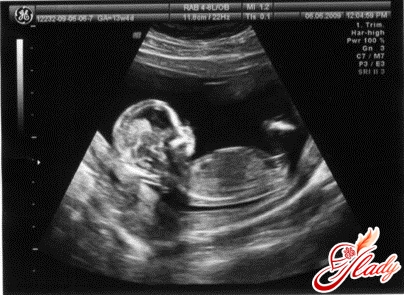

Узи на 13 неделе беременности

Беременность 13 неделя: узи. На данном этапе беременности плацента уже полностью сформирована, скоро начнет самостоятельно производить гормоны прогестерона и эстриола. К тринадцатой неделе плод полностью обволакивает мутноватая мембрана, пуповина отходит наверху с левой стороны. Если у вас беременность 13 неделя, ваш малыш подрос и стал размером с персик. Его длина около 65-78 мм, а вес — от 14 до 20 грамм.